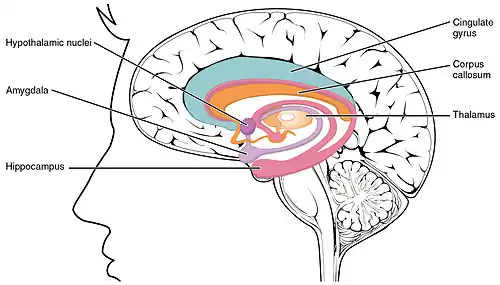

LENAS is seen with damage to the white matter and axons within the brain. The external human LENAS brain shows findings in several major structures. There is mild atrophy of the frontoparietal regions of the brain and a mild reduction of the thalamus and rostral (front) part of the caudate nucleus (which is located in an area of the brain called the basal ganglia).[5] Abnormalities in the frontal, frontoparietal, and temporal lobes are most severe and predominant with LENAS and asymmetry of the cerebral hemispheres has sometimes been found.[5] LENAS also may show moderately enlarged lateral ventricles and atrophy in corticospinal tracts as well as in the pons.[5]

- The corpus callosum is variably affected.

Subcortical U-fibers in the brain appear to be relatively spared, meaning they seem to not be involved in most cases but this does not mean they are not always/eventually involved.[5][8] U-fibers represent connections which are between adjacent areas of the brain located within the cortex or deep in the white matter that are one of the last parts of the brain to be myelinated.[8] In LENAS, it has been found that because these U-fibers are last to myelinate normally, they are also last to be affected as the disease progresses.

Normally, the frontal lobe in our brain are important for our higher level executive functions. Predominance of white matter damage in this lobe has been found to be consistent with both the psychiatric and behavioral signs and symptoms pertaining to LENAS.[10] The underlying symptoms seen of frontotemporal dementia seen commonly in LENAS is associated with the temporal lobe damage.[10] There is a large disconnect in the brain between the lobes that reflect the neuropsychiatric symptoms that are common with the disease.[10]